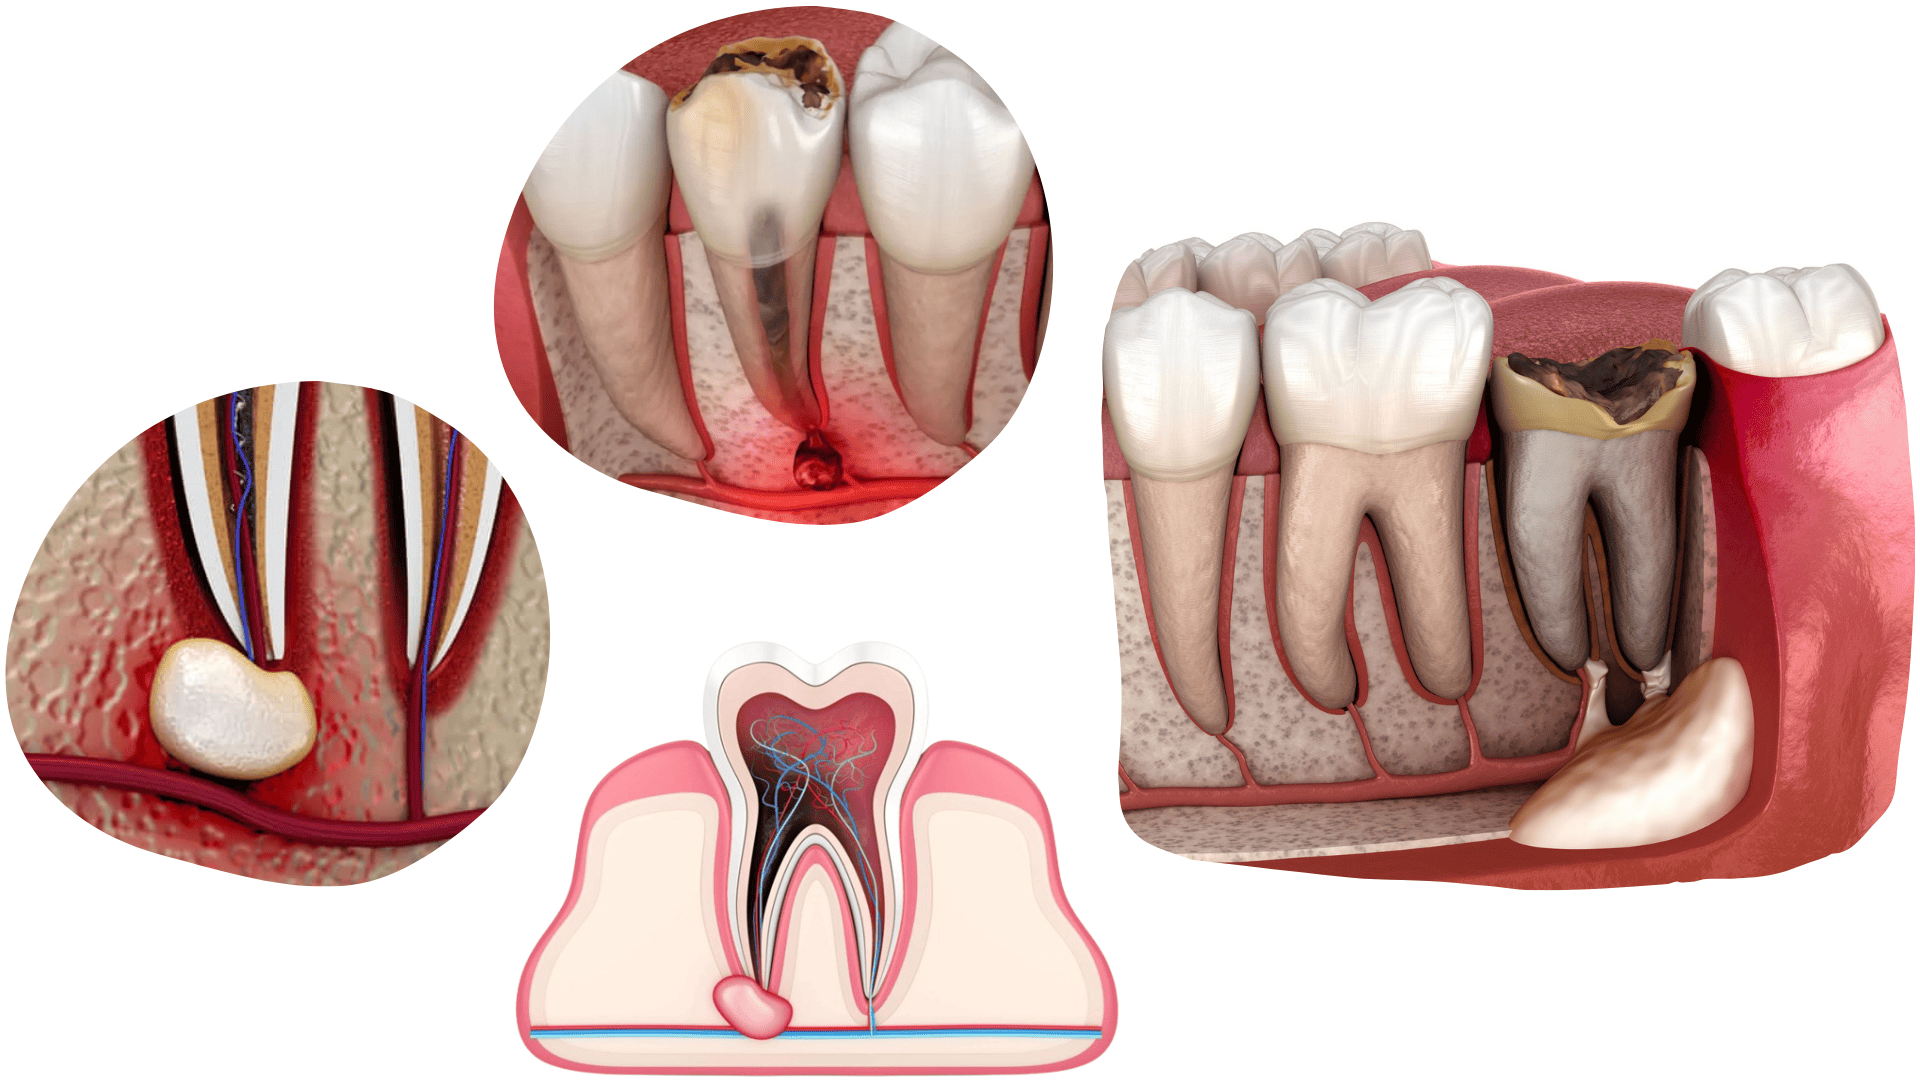

APICOECTOMY

An apicoectomy is an oral surgical procedure in which the tip of the root of a tooth with an inflammatory process is removed.

We perform apicoectomies on teeth where endodontic treatment has failed to resolve the inflammatory process at the root tip.

An apicoectomy is a short and painless procedure performed under local anaesthesia.

CYSTECTOMY

Cystectomy is a surgical procedure for the removal of periapical lesions such as abscesses, granulomas, or various cysts around the tooth root.

These changes are most commonly discovered on a panoramic X-ray when a patient presents with severe pain or swelling. Cysts develop as a consequence of chronic inflammation or unsuccessful endodontic therapy.